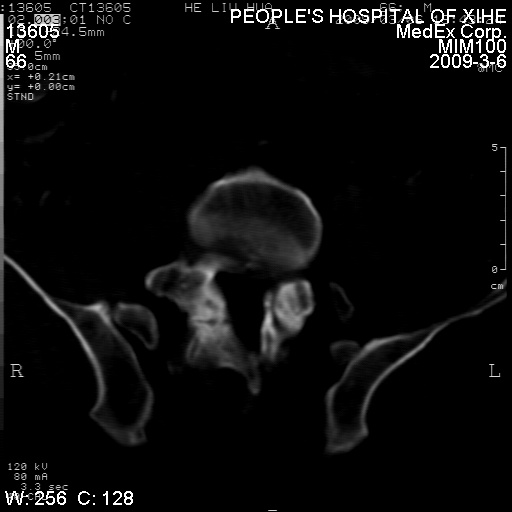

标题: CT18522:男,66岁。考虑结核有错吗 [打印本页]

标题: CT18522:男,66岁。考虑结核有错吗

x线片示:骶骨密度增高。

考虑----腰椎骶化-----退变-----椎管狭窄

腰骶椎退行性改变。

腰骶椎退行性改变,建议重建看看!

退行性变,椎体滑脱

腰椎滑脱并有退变

退行性变,椎体滑脱。建议同椎体平行进一步扫描。